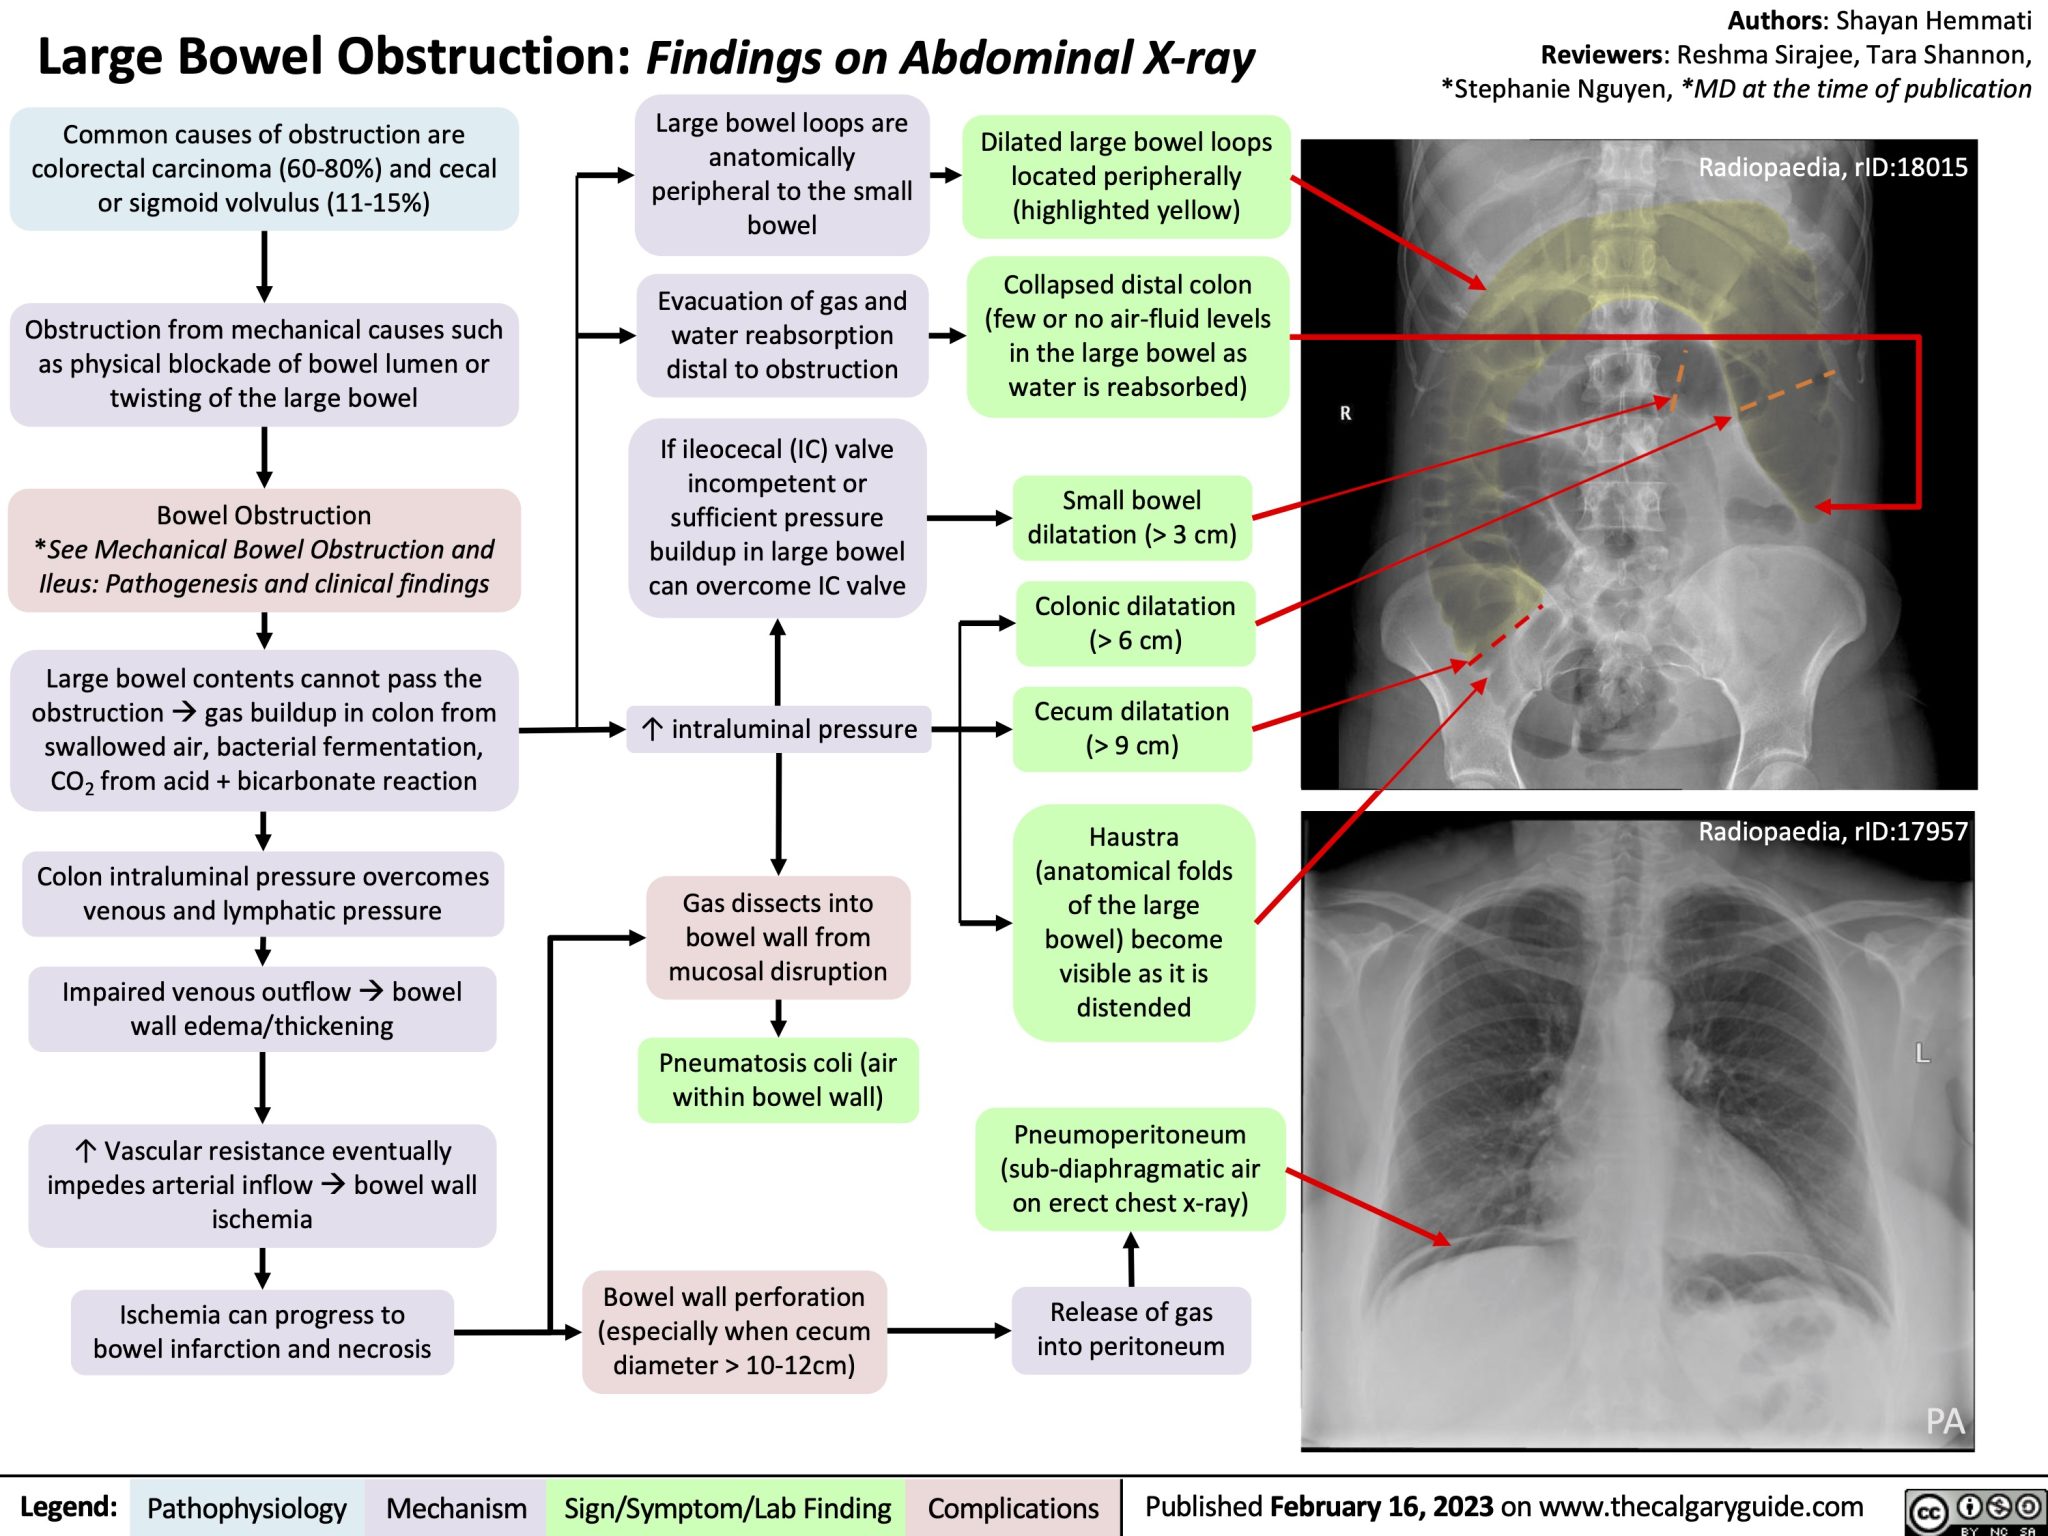

Large Bowel Obstruction Findings On Abdominal X ray Calgary Guide

Large Bowel Obstruction Bowel Obstruction Causes Management